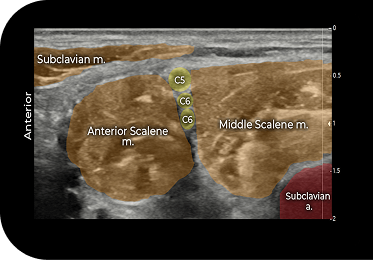

Locate the interscalene brachial plexus

Visualize the C5 to C7 nerve roots

- Place an ultrasound probe on the patient’s neck superior to the clavicle to identify the interscalene brachial plexus between the anterior and middle scalene muscles

- Insert a 20- to 22-gauge echogenic needle into the plane from lateral to medial until the tip is just lateral to the bottom of the interscalene brachial plexus

- Confirm needle position using nerve stimulation and hydrodissection

- Deposit EXPAREL between the anterior and middle scalene muscles until the infiltration around the brachial plexus is documented by ultrasound

ASM, anterior scalene muscle; C5 to C7, cervical nerve roots; DSN, dorsal scapular nerve; LCa, longus capitis; LTN, long thoracic nerve; MSM, middle scalene muscle; RCR, rotator cuff repair; SCM, sternocleidomastoid; TSA, total shoulder arthroplasty; VA, vertebral artery.